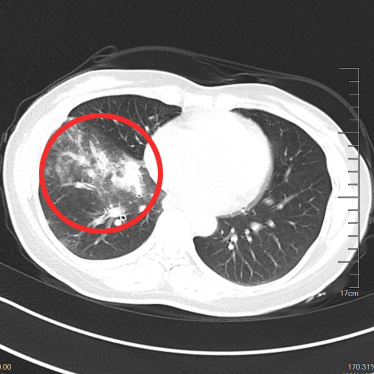

▲治疗后1月

▲治疗后2年半

随访至今

肺部、颅内、可见淋巴结、腹腔等

多处病灶完全缓解

患者日常生活无异于常人